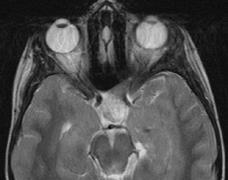

Fig. 7. Neurofibromatosis type 2: Images of a 12-year-old boy with deafness and weakness in his arms and legs, whose father has bilateral deafness. Axial T2-weighted (a) and postcontrast axial (b) T2-weighted images reveal bilateral vestibular schwannomas, which are also known as acoustic neuromas (arrows). This is the classic finding of NF2. (b, c) Bilateral schwannomas are seen in Meckel's cave (arrowheads) and a (d) lower left cranial nerve schwannoma extends into the pars nervosa of the jugular foramen (arrow). (e) A part cystic and part solid enhancing ependymoma in seen within the cervical cord and medulla and within the distal cord and conus. (e, f) Thoracic schwannomas are present at numerous levels (arrowheads). Marked enhancement and thickening of the roots within the cauda equina also represent multiple schwannomas.